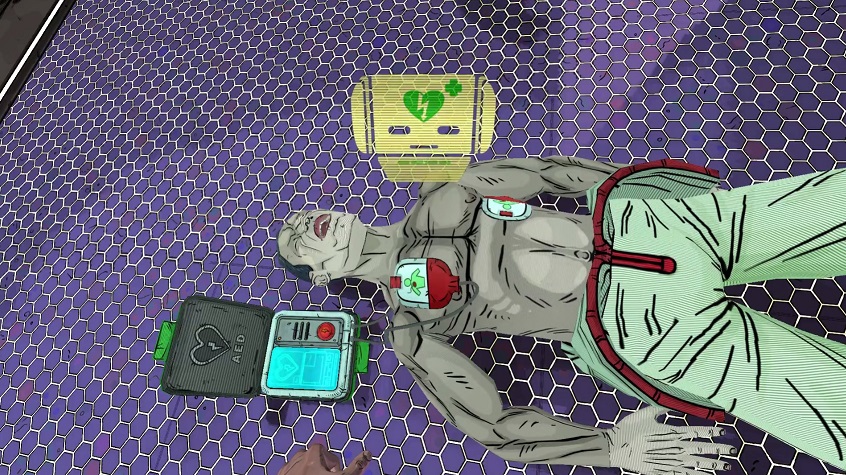

Relive, un videogame per imparare a salvare la vita

Con un videogame le manovre salvavita si imparano con semplicità. A dimostrarlo uno studio condotto su 65 studenti di Pisa e Bologna